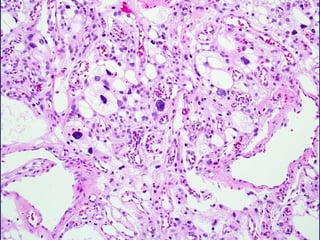

MENINGIOMA ANAPLASICO

• Histológicamente francamente maligno

(similar a sarcoma, carcinoma o melanoma

focal o difusamente) o un alto índice mitotico

(20 o más mitosis por 10 HPF)

MENINGIOMA ANAPLASICO • Histológicamentefrancamente maligno (similar a sarcoma, carcinoma o melanoma focal o difusamente) o un alto índice mitotico (20 o más mitosis por 10 HPF)